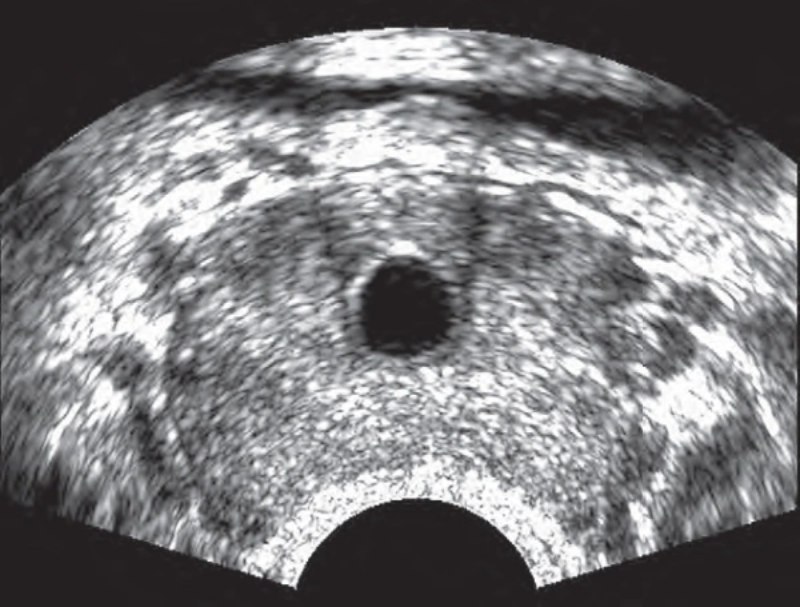

Áp xe tuyến tiền liệt là tình trạng hình thành ổ mủ ở vùng tuyến tiền liệt. Đây là biến chứng của viêm tuyến tiền liệt do vi khuẩn cấp tính.

Hình ảnh siêu âm áp xe tuyến tiền liệt cho thấy một cấu trúc có ranh giới rõ ràng, được bao bọc bởi một vỏ, bên trong chứa dịch có đặc tính trống âm hoặc giảm âm. Khi ổ áp xe phát triển lớn, nó có thể làm thay đổi cấu trúc giải phẫu của tuyến tiền liệt. Trong trường hợp mạn tính, nhu mô vùng ngoại vi trở nên không đồng nhất về hồi âm và thường xuất hiện nhiều nốt vôi hóa nhỏ rải rác.